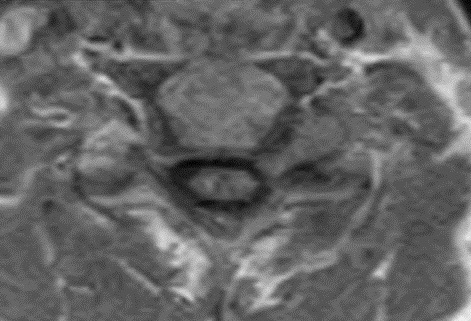

This patient underwent a second limited contrast examination. Pre- and post-contrast T-1 weighted images were obtained. Fig. 4 represents the pre-contrast T-1 weighted image, and Fig. 5 represents the post-contrast image at the same level. There is a quite definite increase in signal intensity of the mass on the post-contrast images. Thus, the mass is said to enhance and this is indicative of a neoplastic process. The most common extradural intraforaminal mass is a schwannoma, which represents a nerve sheathe tumor. This was the presumptive diagnosis as the patient underwent surgery for removal of the tumor. Subsequent biopsy of the lesion confirmed schwannoma. The patient did well post- surgery and the left upper extremity symptoms resolved.